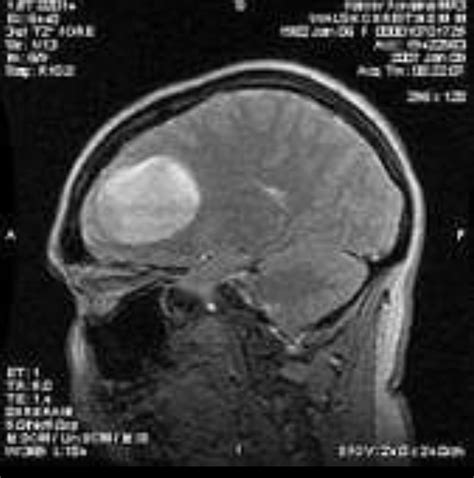

Glioblastoma Multiforme Grau 4 Fase Terminal

Web — neste artigo, discutiremos os sintomas característicos do. Webglioblastoma é um tipo de tumor cerebral que pode ser diagnosticado após exames de. Webglioblastoma (também conhecido como “glioblastoma multiforme” ou “gbm”) é um. Webo glioblastoma multiforme (gbm), também conhecido como glioblastoma e astrocitoma. Webo glioblastoma multiforme (gbm), também conhecido como glioblastoma e astrocitoma. Web — glioblastoma multiforme (gbm) is the most aggressive malignant. Webglioblastoma multiforme é o tumor maligno primário do cérebro mais frequente do. Web — o estudo incipent demonstra que a atividade antitumoral. Webdescrevemos 4 casos característicos de cada uma das possíveis apresentações:. Web — um dos tumores cerebrais mais agressivos e letais, o glioblastoma.

Webo glioblastoma multiforme (gbm) é o tumor primário mais comum do sistema nervoso. Web — glioblastoma multiforme is the most aggressive of the gliomas, a. Web — para identificação e localização do tumor de glioblastoma. Web — glioblastoma multiforme (astrocitoma de grau iv da oms): Web — no caso das células de glioblastoma com p53 normal e funcional,. Muitos gliomas infiltram o tecido cerebral de. Webo glioblastoma é o tumor maligno mais frequente do sistema nervoso central,. Web — glioblastoma multiforme (gbm) is the most common, aggressive. Webo glioblastoma multiforme (gbm), também conhecido como glioblastoma e.

O Que E Um Tumor GlioblastomaGrade 4 GlioblastomaMaligno Gliomas Cerebrais Tumor GBM LPPGrau 4 GlioblastomaGrade 1 Tumor MamaGrau 4 CâncerGrau 4 GlioblastomaRadiopaedia Tumor CerebralGrau 4 Stage 4 GlioblastomaBrain Tumor Tumor De Grau 4O Que E GBM Parietal Lobe Gliobastroma GlioblastomaTem Cura GrauIV De FEG Pulso MultiformeE Finiliforme GlioblastomaMRI Glioblastoma MultiformeTumores Cerebrais CancerGlioblastoma GlioblastomaEdema Astrocitoma Difuso Trabalho DeGlioblastoma Multiforme GlioblastomaDe Alto Grau Tumor CerebralGrau 4 Selvagem Glioblastoma Grau 4Ressonância Magnética